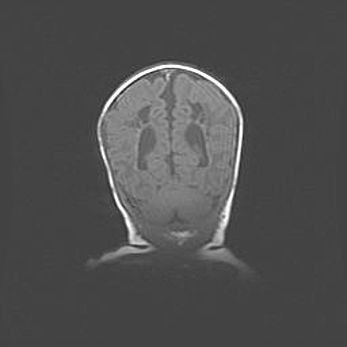

Открытая гидроцефалия.

Возраст: 9 месяцев 12 дней

Вес: 6800 г

Пол: мужской

Окружность головы: 41,5 см

Срок гестации: 28 недель

Гидроцефалия головного мозга у новорожденных имеет характерный признак: опережающий рост окружности головы приводит к визуально хорошо определяемой гидроцефальной форме сильно увеличенного в объёме черепа. Детские неврологи определяют следующие симптомы гидроцефалии у грудничков: выбухающий напряжённый родничок, частое запрокидывание головы, смещение глазных яблок к низу.